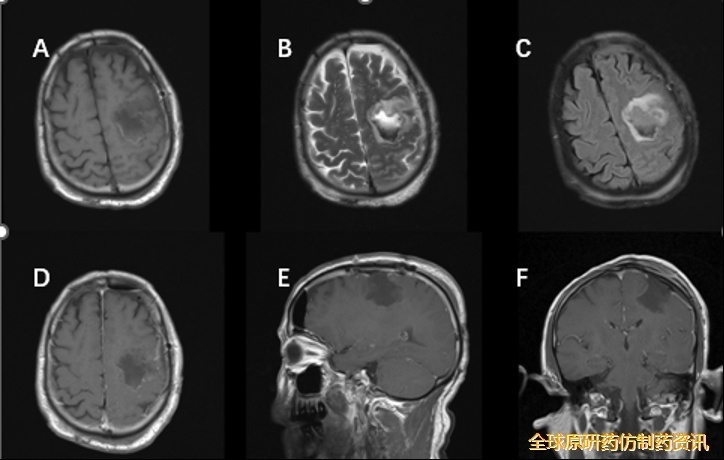

入院后完善常规检查,各项指标未见异常。头颅MRI增强扫描显示:1、左侧额叶见类圆形占位性病变,大小约3.8×3.1×3.2 cm,边界清晰,周围轻度水肿,增强扫描示实性成分明显强化(图1);2、MRS示病灶侧对比镜像侧Cho/NAA比值显著升高;3、DTI示左侧额顶部皮质脊髓束受压移位伴局部缺损,余白质纤维束走行正常。结合临床表现与影像学特征,初步诊断为:左侧额叶高级别胶质瘤。

图1.患者术前头颅MRI显示左侧额叶病变部位

完善术前准备,排除手术禁忌后,患者于2019年3月行黄荧光引导下左侧额叶肿瘤切除术+硬膜修补+颅骨成形术。术中标记左侧额颞顶部马蹄形切口,游离骨瓣,剪开硬膜翻向中线。显微镜下沿肿瘤皮层造瘘,见肿瘤呈灰红色、质地稀软、血运差、边界清晰,沿囊壁完整切除肿瘤,达显微镜下全切除。术后患者恢复顺利,未见神经功能症状加重。术后常规复查头颅增强MRI提示肿瘤全切(图2)。

图2.术后头颅MRI增强扫描显示肿瘤全部切除